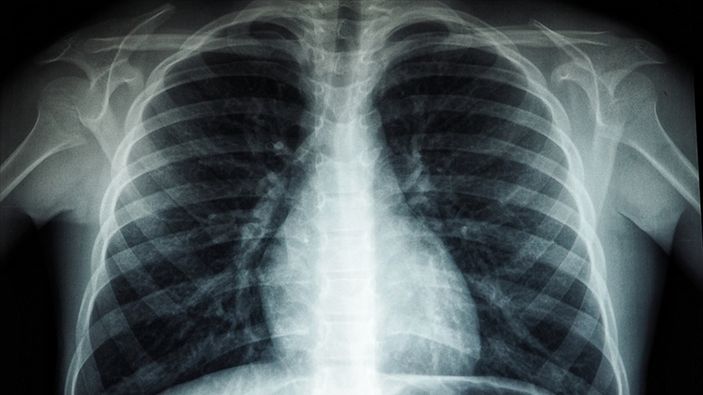

Beyaz akciğer sendromu nedir

Bu sendromu, akciğerlerin ani bir şekilde iltihaplanması sonucu oluşan, hayati organlara yeterli oksijen gitmeyen ciddi bir durumdur.

Akciğerde kalsiyum birikirse (kalsiyum oksit, kalsiyum karbonat, kalsiyum sülfat gibi kimyasallara uzun süreli maruz kalınan mesleklerde) akciğer filminde beyaz lekelenmeler görülür.